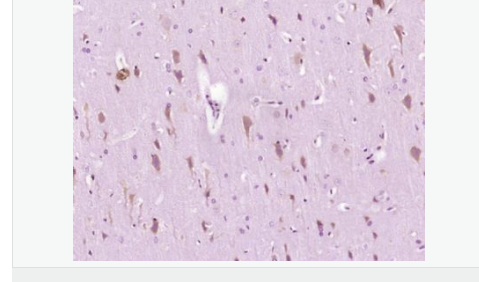

| 產品應用 | ELISA=1:5000-10000 IHC-P=1:100-500 IHC-F=1:100-500 Flow-Cyt=1ug/test ICC=1:100-500 IF=1:100-500 (石蠟切片需做抗原修復) not yet tested in other applications. optimal dilutions/concentrations should be determined by the end user. |

| 產品介紹 | The protein encoded by this gene is the ER to nucleus signalling 1 protein, a human homologue of the yeast Ire1 gene product. This protein possesses intrinsic kinase activity and an endoribonuclease activity and it is important in altering gene expression as a response to endoplasmic reticulum-based stress signals. [provided by RefSeq, Jul 2008] Function: Senses unfolded proteins in the lumen of the endoplasmic reticulum via its N-terminal domain which leads to enzyme auto-activation. The active endoribonuclease domain splices XBP1 mRNA to generate a new C-terminus, converting it into a potent unfolded-protein response transcriptional activator and triggering growth arrest and apoptosis. Subunit: Homodimer; disulfide-linked. Dimer formation is driven by hydrophobic interactions within the N-terminal luminal domains and stabilized by disulfide bridges. Also binds HSPA5, a negative regulator of the unfolded protein response. This interaction may disrupt homodimerization and prevent activation of ERN1. Interacts with TAOK3 and TRAF2. Subcellular Location: Endoplasmic reticulum membrane. Tissue Specificity: Ubiquitously expressed. High levels observed in pancreatic tissue. Post-translational modifications: Autophosphorylated. Similarity: Belongs to the protein kinase superfamily. Ser/Thr protein kinase family. Contains 1 KEN domain. Contains 1 protein kinase domain. SWISS: O75460 Gene ID: 2081 Database links: Entrez Gene: 2081 Human Entrez Gene: 78943 Mouse Omim: 604033 Human SwissProt: O75460 Human SwissProt: Q9EQY0 Mouse Unigene: 133982 Human Unigene: 592041 Human Unigene: 700027 Human Unigene: 20452 Mouse Unigene: 340943 Mouse Unigene: 226435 Rat Important Note: This product as supplied is intended for research use only, not for use in human, therapeutic or diagnostic applications. |